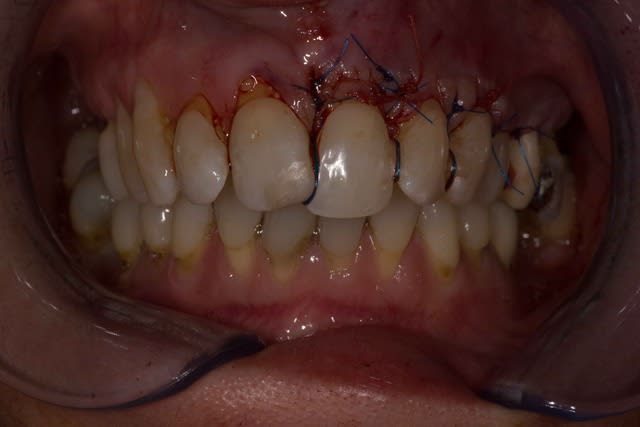

Img 2078 jexjqo - Eugenol

Img 2079 zq4nhx - Eugenol

Img 2076 afcxn3 - Eugenol

tillcky luke : l'homme qui dégaine son scalpel plus vite que son ombre.

Effectivement David tu ne pouvais pas mettre en application de façon plus rapide.

Merci de poster ce cas et ta chirurgie même si tu sais ce que je pense de la technique de tunnélisation ;-))

Oui effectivement et la j'ai trouvé la limite de cette technique j'ai pas bien réussi a tracter mon lambeau :/.

Je pense qu'a partir de maintenant je vais me mettre au LDC histoire de me faire vraiment la main avec cette technique.